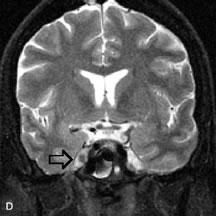

MRI and MRV are more sensitive than CT in revealing cavernous sinus thrombosis. Engorgement of the cavernous sinus, extraocular muscles, and ophthalmic veins is seen with hyperintensity of the thrombosed sinuses evident on all pulse sequences. The enlarged, thrombosed superior ophthalmic vein appears less hypointense than the normal contralateral ophthalmic vein, and hyperintensity within the lumen of the vessel may be seen on T1- and T2-weighted MR images.68